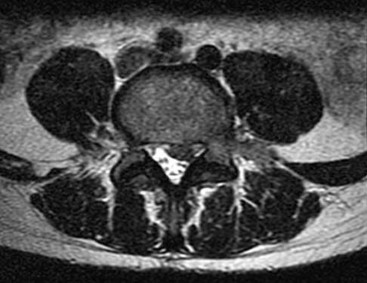

Question 13:

A 65-year-old male presents with neurogenic claudication. He reports pain radiating down both legs when walking, which is relieved by leaning forward on a shopping cart. MRI shows severe spinal stenosis at L4-L5. Which ligament thickens and contributes significantly to the dorsal compression of the thecal sac in this condition?

Correct Answer: Ligamentum flavum

Explanation:

In degenerative lumbar spinal stenosis, hypertrophy and buckling of the ligamentum flavum commonly cause dorsal compression of the thecal sac.